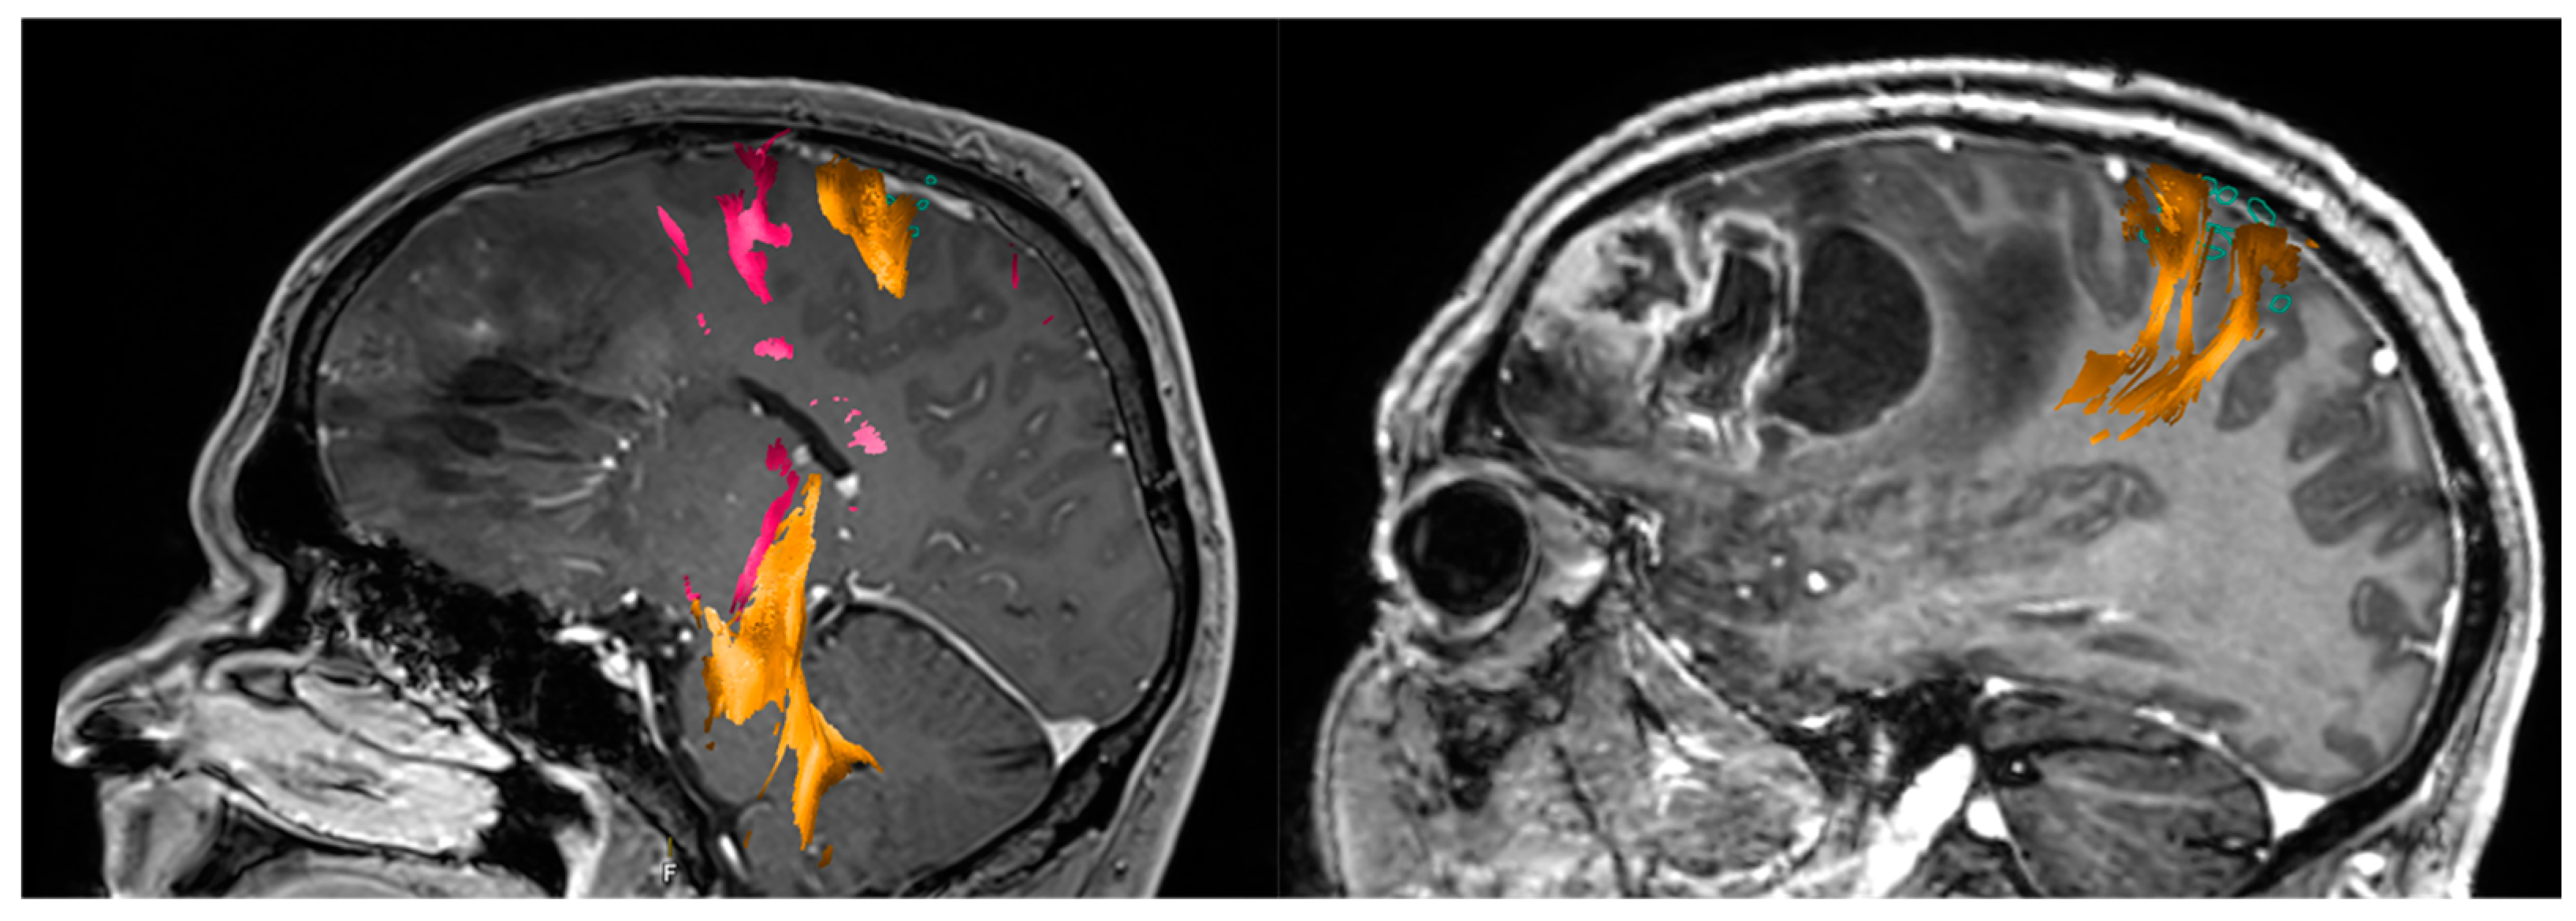

- Abdullah, K.G.; Lubelski, D.; Nucifora, P.G.P.; Brem, S. Use of diffusion tensor imaging in glioma resection. Neurosurg. Focus 2013, 34, E1. [Google Scholar] [CrossRef] [PubMed] [Green Version]

- Bello, L.; Gambini, A.; Castellano, A.; Carrabba, G.; Acerbi, F.; Fava, E.; Giussani, C.; Cadioli, M.; Blasi, V.; Casarotti, A.; et al. Motor and language DTI Fiber Tracking combined with intraoperative subcortical mapping for surgical removal of gliomas. NeuroImage 2008, 39, 369–382. [Google Scholar] [CrossRef]

- Raffa, G.; Bährend, I.; Schneider, H.; Faust, K.; Germanò, A.; Vajkoczy, P.; Picht, T. A Novel Technique for Region and Linguistic Specific nTMS-based DTI Fiber Tracking of Language Pathways in Brain Tumor Patients. Front. Neurosci. 2016, 10, 552. [Google Scholar] [CrossRef]

- Romano, A.; D’Andrea, G.; Minniti, G.; Mastronardi, L.; Ferrante, L.; Fantozzi, L.M.; Bozzao, A. Pre-surgical planning and MR-tractography utility in brain tumour resection. Eur. Radiol. 2009, 19, 2798–2808. [Google Scholar] [CrossRef]

- Sollmann, N.; Kelm, A.; Ille, S.; Schröder, A.; Zimmer, C.; Ringel, F.; Meyer, B.; Krieg, S.M. Setup presentation and clinical outcome analysis of treating highly language-eloquent gliomas via preoperative navigated transcranial magnetic stimulation and tractography. Neurosurg. Focus 2018, 44, E2. [Google Scholar] [CrossRef]